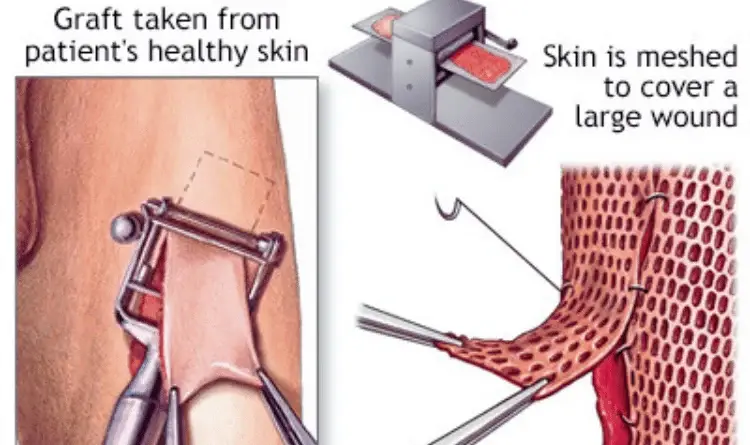

Skin Grafts

We provide advanced skin grafting techniques for wound coverage, burns, and post-traumatic defects. Our approach ensures optimal healing, functional recovery, and aesthetic integration. Performed with precision for reliable, long-term outcomes.